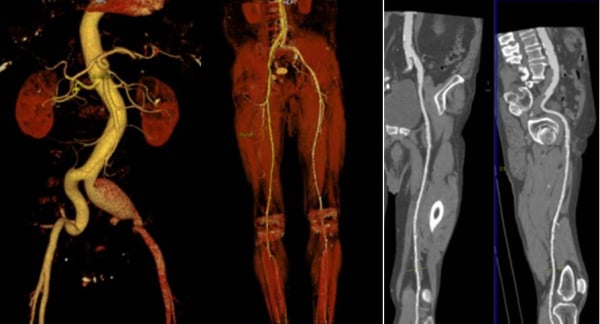

Ένα σύγχρονο και τεχνολογικό ιατρείο αγγειοχειρουργού θα ενσωματίζει πολλές σύγχρονες τεχνολογίες και πρακτικές προκειμένου να παρέχει υψηλής ποιότητας φροντίδα για προβλήματα που σχετίζονται με τον αγγειακό σύστημα. Ορισμένα χαρακτηριστικά που μπορεί να έχει ένα τέτοιο ιατρείο περιλαμβάνουν: